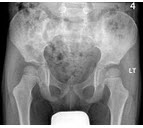

男,根据其正常骨盆影像图像,判断其最可能的年龄()

A.6岁左右

B.30岁左右

C.12岁左右

D.18岁左右

E.24岁左右